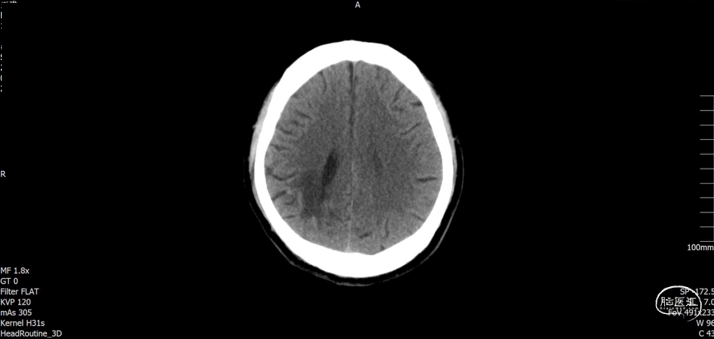

现病史:患者于入院前2小时在工地干活时被高空坠物砸伤头部(具体过程不详),伤后出现左侧肢体活动失灵,被同事送往我院急诊科就诊,入急诊时神志清醒,GCS15分,行颅脑CT提示:1. 右侧颞顶骨骨折,顶骨多发骨折并部分嵌插脑内;2. 右侧顶叶脑挫伤;3. 右侧额颞顶部硬膜下血肿;4. 蛛网膜下腔出血。急诊予以清创、止血及对症治疗。期间患者意识障碍加重呈嗜睡,GCS14分,我科急会诊后以“1. 开放性颅脑损伤特重型 1.1开放性颅内异物1.2脑挫裂伤1.3蛛网膜下腔出血1.4颞顶骨骨折(右);2. 偏瘫(左)”收住入院。自发病来,患者暂无抽搐、晕厥等症状,小便失禁。

入院查体:右顶部头皮见长约2.0cm开放性伤口,出血并脑脊液漏出,颅骨嵌入。神志嗜睡,GCS评分:E3+V5+M6=14分。双侧瞳孔等大正圆,直径均约3.0mm,直、间接对光反射灵敏。左侧上下肢肌力约I/0级,右侧上下肢肌力约IV/IV级。

入院检查

![]()